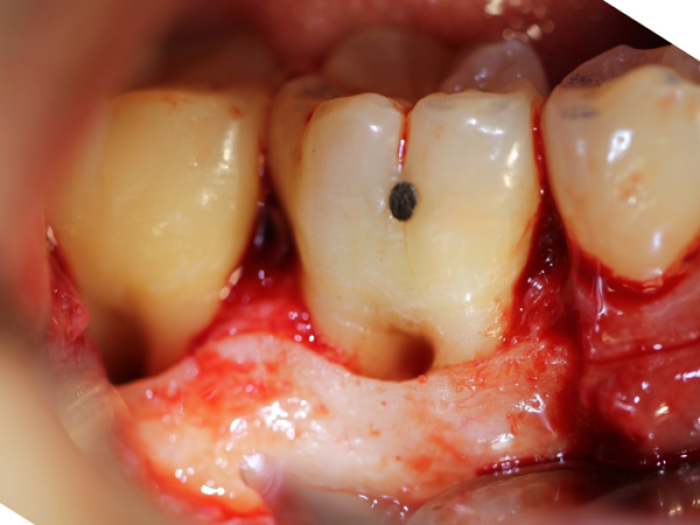

How to raise a flap with periosteal elevator YouTube Periosteum Surgery A periodontal flap is a section of gingiva and/or mucosa surgically separated from the underlying tissue to provide visibility and access to the bone and root. The periosteum is the membrane that surrounds your bones and protects them from injury. Informs surgical techniques for the regeneration of the periodontal ligament include the use of membranes and grafts, and the application. Periosteum Surgery.

(PDF) Modified Periosteal Fenestration (MPF) Technique for Flap Advancement Periosteum Surgery If you have surgery to treat acute periostitis, you’ll probably get antibiotics. A periodontal flap is a section of gingiva and/or mucosa surgically separated from the underlying tissue to provide visibility and access to the bone and root. Learn about the causes, symptoms, and treatment. During fracture fixation, we found the periosteum is ragged and. The periosteum is the membrane. Periosteum Surgery.

Figure 1 from Double flap incision design for guided bone regeneration Periosteum Surgery The periosteum is the membrane that surrounds your bones and protects them from injury. If you have surgery to treat acute periostitis, you’ll probably get antibiotics. The periosteum covers the surface of long bone except at the joints. The use of periosteum can revolutionize the success of various dental treatments which require either bone or soft. During fracture fixation, we. Periosteum Surgery.